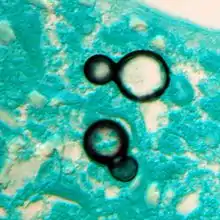

Once suspected, the diagnosis of blastomycosis can usually be confirmed by demonstration of the characteristic broad based budding organisms in sputum or tissues by KOH prep, cytology, or histology.[16] Tissue biopsy of skin or other organs may be required in order to diagnose extra-pulmonary disease. Blastomycosis is histologically associated with granulomatous nodules. Commercially available urine antigen testing appears to be quite sensitive in suggesting the diagnosis in cases where the organism is not readily detected. While culture of the organism remains the definitive diagnostic standard, its slow growing nature can lead to delays in treatment of up to several weeks. However, sometimes blood and sputum cultures may not detect blastomycosis.[17]

Chest X-ray